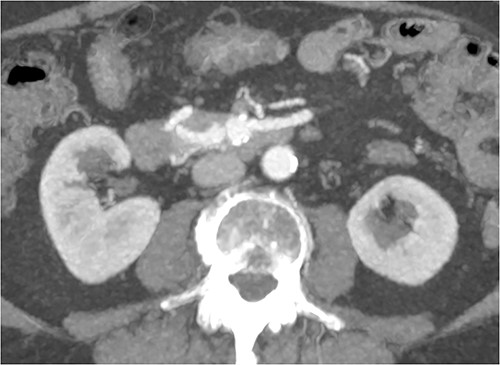

CT of abdomen and pelvis was performed, which revealed a 13 mm indeterminate lesion arising between the pancreatic uncinate process and the duodenum with coarse peripheral calcification, suspicious of primary pancreatic neoplasm or primary small bowel cancer (Figs 2–4).

Initial CT: axial view, demonstrating what was initially thought to represent indeterminate pancreatic/duodenal lesion.

A multiphase CT of the pancreas had unexpected findings. There were no pancreatic masses on the arterial and portal phase study, and no paraaortic or mesenteric lymphadenopathy. The abnormal calcification seen on the previous study corresponded to a dilated vessel along the superior margin of the pancreatic body. This dilated vessel was an abnormal communication between a tortuous ecstatic gastroduodenal artery and the first branch of the SMA, a Buhler’s arc communication. The celiac axis origin was narrowed >90%. No other suspicious solid organ mass lesion was identified. Soft tissues were unremarkable (Figs 5–8).

Multiphase CT pancreas, axial view demonstrating abnormal communication between the CA and the SMA.